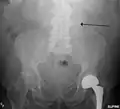

The faint outline of the calcified wall of an AAA as seen on a plain X-ray- Abdominal aortic aneurysms (3.4 cm)